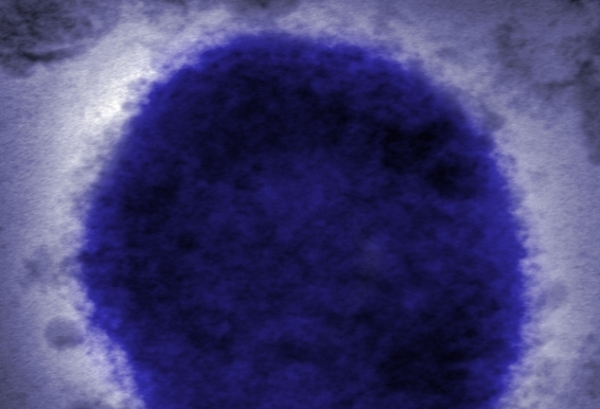

تشهد أوروبا حاليا أكبر انتشار لحالات جدري القرود في تاريخها، حيث أعلنت إسبانيا والبرتغال عن حالات مؤكدة ومشتبه بها.

وعادة ما يظهر الفيروس، وهو أحد أقارب الجدري، كمرض خفيف لا يستمر أكثر من بضعة أسابيع.

ويمكن أن يسبب الحمى والصداع والطفح الجلدي، والتي قد تسبب بثورا مماثلة لتلك التي تظهر مع انتشار جدري الماء.